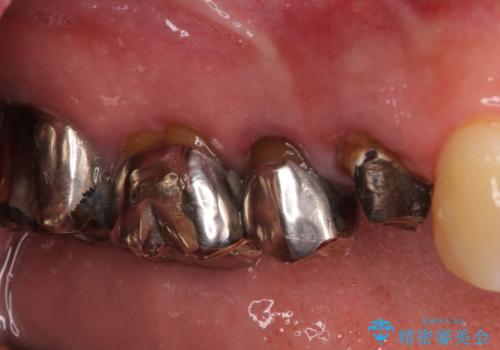

- 奥歯に違和感を感じており、抜歯の必要性を感じて来院された患者様です。

診査の結果、5本の奥歯を抜歯してインプラントによる補綴治療が必要と診断されました。

左上の奥歯は2本抜歯が必要であったため、治療期間中は右側に負担がかかり、頻繁に仮歯が壊れてしまいました。